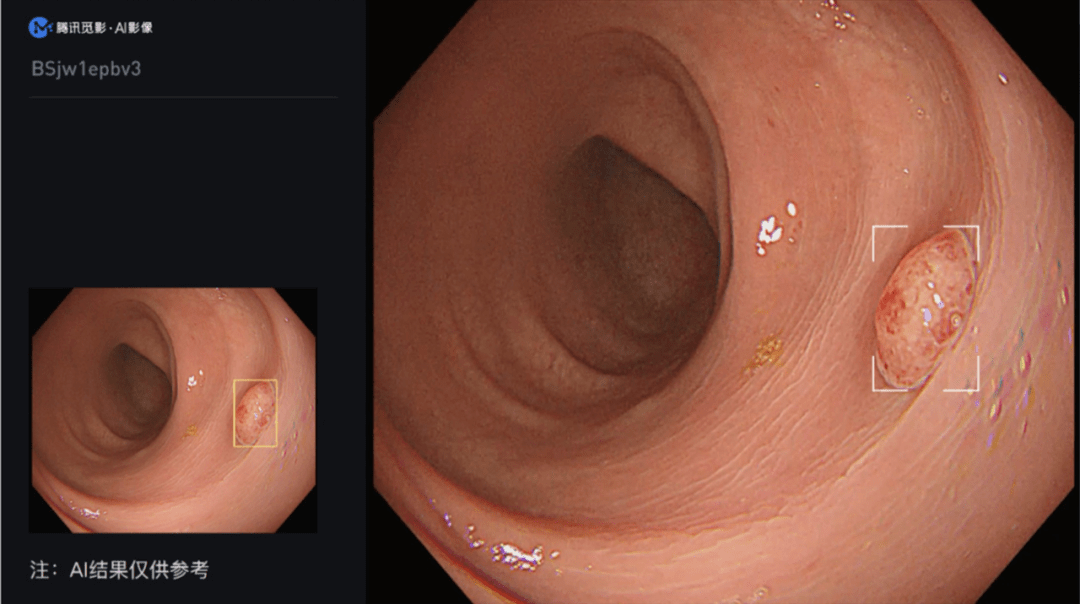

2023年6月1日,国家药品监督管理局公告:腾讯觅影旗下产品“结肠息肉电子内窥镜图像辅助检测软件”获批上市。这项通过创新医疗器械审查的人工智能辅助检测产品,有助于提升息肉检出率,辅助临床医生更高效、精准发现结肠息肉,从而降低结肠癌的发生率和死亡率。

“结肠息肉电子内窥镜图像辅助检测软件”需配合结肠镜检查,从电子内窥镜图像处理器输出的视频流中导入视频图像信号,经过深度学习算法分析后将疑似息肉位置在视频中进行实时标记,提醒医生关注疑似病灶。